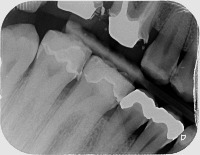

Caries Dentaires Computer Vision Project

Dental Health Diagnosis: Healthcare professionals can use the model to facilitate the early detection and categorization of caries dentaires, helping them identify the severity of the decay, and plan the most effective treatment.

Dental Education: Dental schools can use the model as a teaching tool, helping students understand the different stages of tooth decay and honing their diagnostic skills through digital practice cases.

Dental Insurance Assessment: Insurance companies can use the model to categorize the severity of customers' dental issues, aiding them in creating more comprehensive and accurate coverage plans.

Dental Research: Researchers studying oral health can use the model in their studies to better understand the progression of tooth decay and develop new treatments or prevention methods.